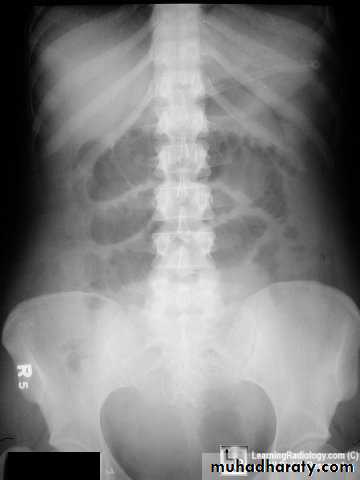

Sigmoid volvulus

Inverted U-shaped appearance of distended sigmoid loopLargest and most dilated loops of bowel are seen with volvulus

Loss of haustra

Coffee-bean sign à midline crease corresponding to mesenteric root in a greatly distended sigmoid

Sigmoid volvulus – bowel loop points to RUQ

Cecal volvulus – bowel loop points to LUQ